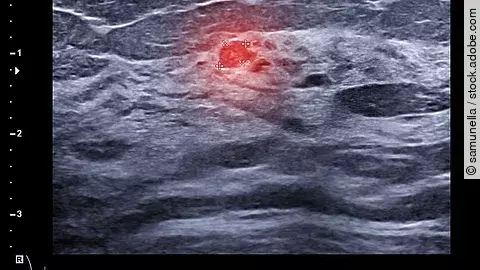

Ultraschalluntersuchungen können dank Künstlicher Intelligenz noch leistungsstärker sein. Weniger schonende Bildgebungsverfahren könnten dadurch ergänzt oder sogar abgelöst werden. Einsatzgebiete gibt es bereits im Bereich der Mammasonographie.